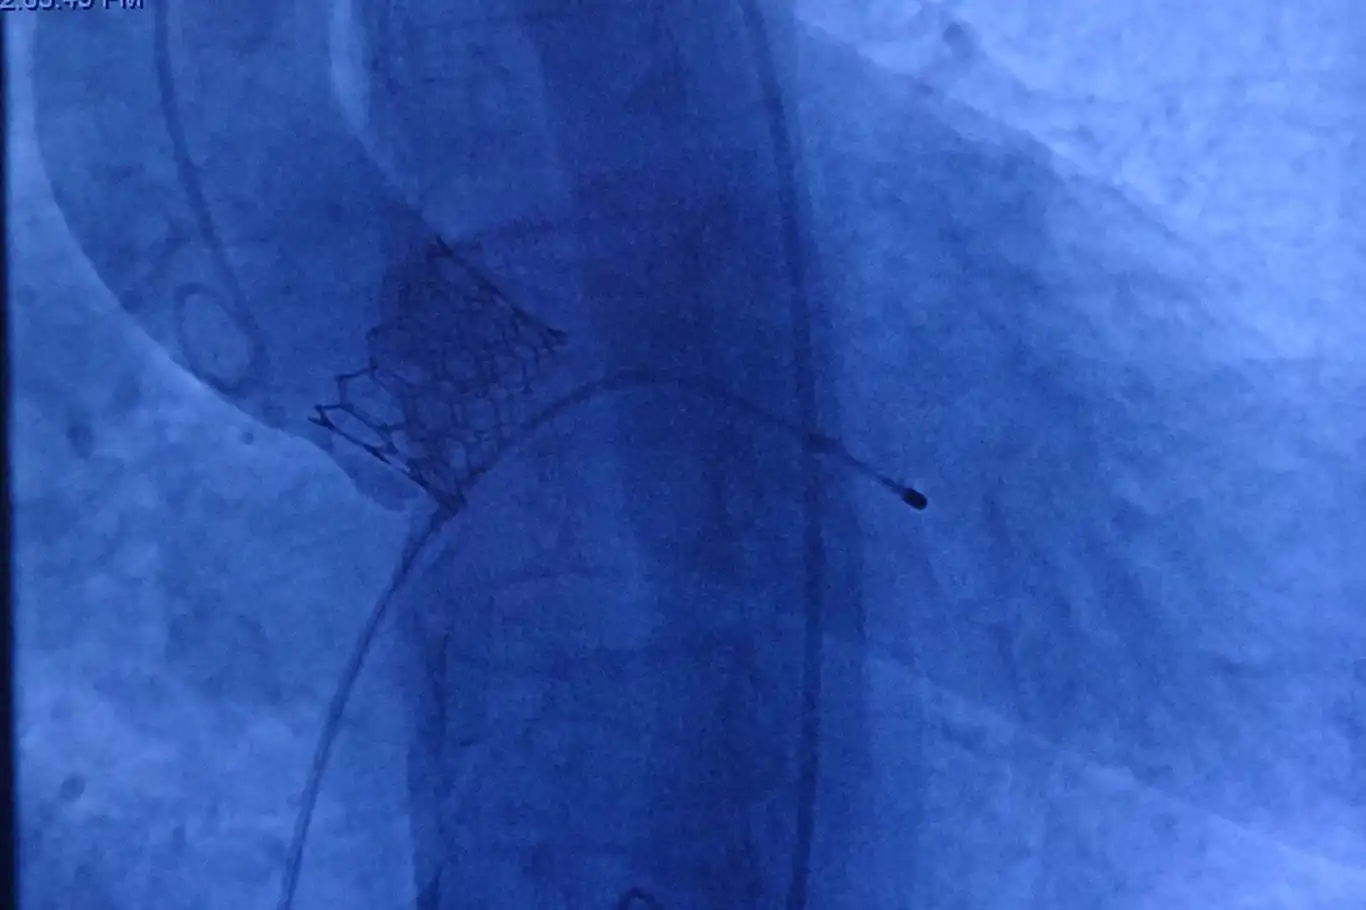

Nefes darlığı, göğüs ağrısı ve ciddi baş dönmesi şikayetleri ile Diyarbakır'dan Malatya Turgut Özal Tıp Merkezine başvuran, yapılan ekokardiyografisinde ileri derece aort darlığı tespit edilen 78 yaşındaki kadın hasta, Anjiyo yöntemiyle kalp kapağı başarılı bir şekilde değiştirilerek sağlığına kavuştu.

"Nefes darlığı, göğüs ağrısı ve son dönemde ciddi baş dönmeleri yaşayan hastamızın ekokardiyografisinde ileri derece aort darlığı tespit ettik. Açık ameliyatın yüksek riskli olması nedeniyle, kalp cerrahları ile yaptığımız değerlendirme sonucunda TAVI yöntemini uygulama kararı aldık. Anjiyo yöntemiyle kalp kapağını başarılı bir şekilde değiştirdik ve hastamız sağlığına kavuştu."

Her ay ortalama 8 ila 10 hastaya bu yöntemin uygulandığını belirten Pekdemir, "Kapalı yöntemle yapılan bu işlem, hasta için son derece konforlu. Açık kalp ameliyatında olduğu gibi göğüs kafesi kesilmiyor, kalp durdurulmuyor ve sadece kasıktan küçük bir delikle girilerek işlem gerçekleştiriliyor. Hastalar ikinci gün servise alınıyor ve genellikle üçüncü gün taburcu ediliyor. Özellikle yaşlı hastalar için bulunmaz bir yöntem" şeklinde konuştu.